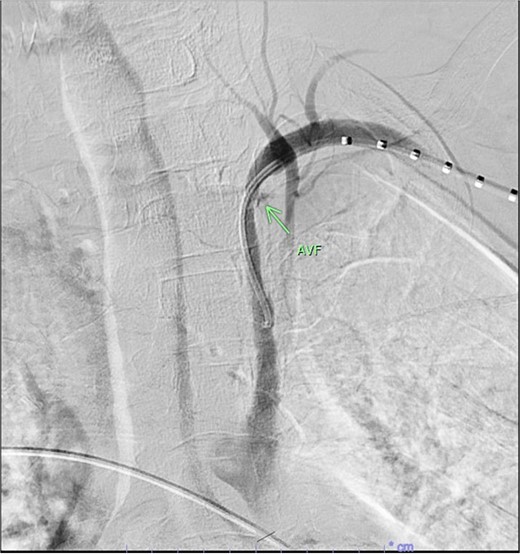

A 67-year-old male with a medical history significant for hypertension, diabetes, coronary artery disease, carotid artery stenosis, osteoarthritis, and 50 pack-year smoking history presented initially to an orthopedic surgery office for evaluation of left shoulder pain after exercising. The patient was found to have an underlying rotator cuff injury and was subsequently treated with cortisone injection. The patient subsequently developed septic arthritis, ultimately requiring incision and drainage of the abscess and resection of the sternoclavicular joint, partial first rib, and partial clavicle. The patient required multiple washouts and debridement procedures, ultimately leading to septic shock and bacteremia requiring close observation in the surgical intensive care unit. A computed tomography angiogram (CTA) of chest was performed at the time and revealed a subcentimeter penetrating ulcer, arising from the proximal left subclavian artery likely secondary to surgical trauma, which was observed nonoperatively given the patient critical status in the intensive care unit (ICU) (Figs 1 and 2). During the ICU course, the patient developed left upper extremity swelling A left upper extremity duplex ultrasound subsequently revealed a nonocclusive deep vein thrombosis of the subclavian vein and also showed resolution of a pseudoaneurysm (PSA) of the subclavian artery. The patient was started on anticoagulation at this time for a deep vein thrombosis (DVT). The patient was ultimately discharged upon resolution of his acute infection to a rehabilitation facility. During the third-month follow-up office visit, the fistulous connection between the subclavian artery and vein was found incidentally on left upper extremity duplex ultrasound (Fig. 3). Physical exam of the patient was otherwise unremarkable with palpable upper extremity pulses and the patient did not appear to have any symptoms related to the fistula including upper extremity swelling or open wounds. The patient was scheduled for an elective repair of the fistula via endovascular stent graft placement. The patient was brought to the operating room, and the radial artery was accessed with a micropuncture device. Radial artery access was our choice to intervene given the location of fistula. When left upper extremity angiography was performed, it revealed a blush of contrast from proximal subclavian artery, revealing a small fistula between subclavian artery and subclavian vein (Fig. 4). Subsequently, a 6 × 29 mm balloon-mounted stent graft was used to cover the fistula. Completion angiography was performed showing adequate seal with resolution of the fistula (Fig. 5). The patient tolerated the procedure well and was subsequently discharged from the hospital the same day. He was started on antiplatelet therapy post-operatively and continued oral anticoagulation for the DVT. The patient was seen in the office at 3-month follow-up, where a repeat duplex ultrasound revealed normal waveforms and velocities throughout the left arm. He was also seen in the office recently, and he is doing well with no new complaints.

Demonstration of fistulous connection between subclavian artery and vein (green arrow).